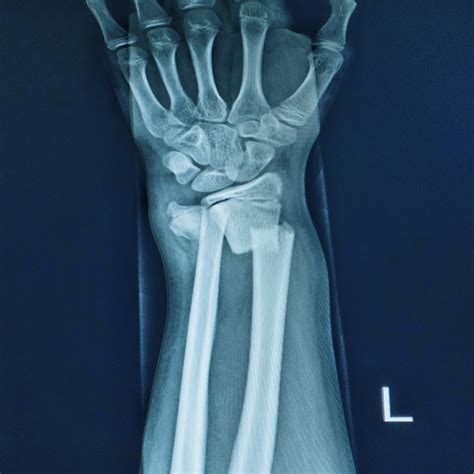

Diagnosing a fracture typically involves a physical examination and imaging tests. X-rays are the most common imaging test used to confirm a fracture. In some cases, additional tests such as CT scans or MRI may be ordered to provide more detailed images of the bone and surrounding tissues.

Understanding Fractures

A fracture, also known as a broken bone, occurs when there is a break or crack in the bone. Fractures can range from minor cracks to complete breaks that pierce the skin. They can affect any bone in the body but are most commonly seen in the arms, legs, and ribs.